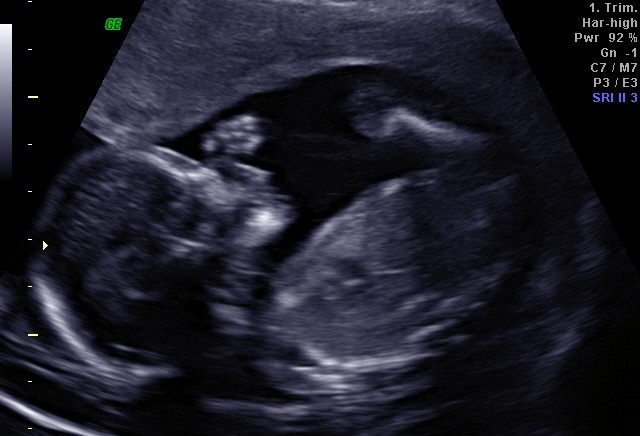

We are being seen regularly, although the consultant we have actually only met once, we have had scans at 9, 12, 14, 17, 20, 22 and 28 weeks. We have further scans booked for 32 and 36 weeks and it is likely this little one will be born a week or two after that, which is a really strange concept as both our boys have been over a week late so I expected to be settling in for 41+ weeks of pregnancy and in all reality this pregnancy will be 38 weeks at most. We generally see a junior doctor when we visit the hospital, which is fine, but generally they don’t know our history, haven’t been given adequate opportunity to read my notes and have no clue what they are supposed to be doing for me. Which given the fact that we had such a horrid previous 2 pregnancies, you would expect them to at least know why we are under consultant care. Andrew being the upfront guy that he is, fills in one of those comment cards every time we go, usually with a blunt and to the point synopsis of our visit, such as ‘visited clinic, saw another new doctor, would be fab if they knew why we are here’.